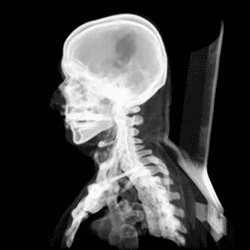

Че́реп (лат. cranium) — костная или хрящевая часть головы[1][2] у позвоночных животных, каркас головы, защищающий от повреждения наиболее уязвимые органы и служащий местом прикрепления её мягких тканей. Он поддерживает структуры лица и создает защитную полость для головного мозга и хорошо защищённые глазницы для глаз[3].

Череп состоит из двух отделов: висцерального (лицевого) и мозгового (черепная коробка). Причём у человека, в отличие от животных, мозговой череп значительно преобладает над лицевым. Все кости черепа, кроме нижней челюсти и подъязычной кости[6], соединены неподвижным соединением[7].

Считается, что человеческий череп состоит из двадцати двух костей — шести костей мозгового черепа и девяти костей лицевого скелета. В нейрокраниуме это затылочная кость (лат. os occipitale), две височные кости (лат. os temporale), две теменные кости (лат. os parietale), клиновидная (лат. os sphenoidale), решётчатая (лат. os ethmoidale) и лобная кости (лат. os frontale)

Костями лицевого черепа являются сошник (лат. os vomer), две нижних носовой раковины (лат. concha nasalis inferior), две носовых кости, две челюсти: пара верхнечелюстных костей (лат. maxilla), одна нижняя челюсть (лат. mandibula), две небные кости (лат. os palatinum), две скуловых кости (лат. os zygomaticum), и две кости слёзных (лат. os lacrimale). Некоторые источники включают подъязычную кость (лат. os hyoideum)[6] или три косточки среднего уха, но в целом общее мнение о количестве костей в человеческом черепе двадцать три, включая подъязычную.

Существуют каналы и отверстия в черепе. Самым большим из них является большое затылочное отверстие, через которое проходит продолговатый и спинной мозг, а также черепные нервы и кровеносные сосуды.